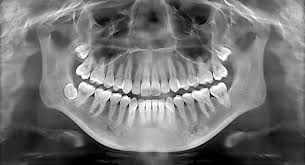

Dental X-Ray

Also known as dental radiographs, dental X-rays use controlled pulses of radiation to create images of the internal structures of the jaw and mouth.

Dental X-rays can show diseases of the mouth, including the teeth and gums, that would otherwise go undetected. These diseases include potentially serious conditions such as the following: An abscess, or infection at the root of a tooth or between the gum and a tooth. Areas of decay that are not visually detectable.